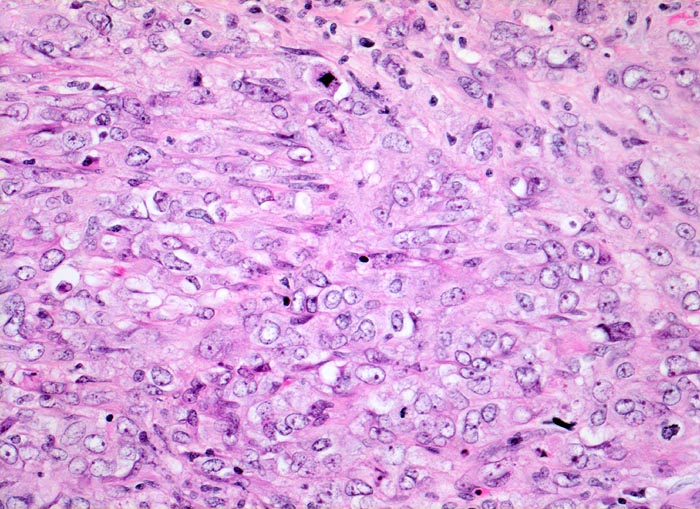

wenig differenziertes Urothelkarzinom

Polymorphe Tumorzellen mit unscharfen Zellgrenzen und bläschenförmigen (=vesikulären) Kernen. Die Tumorzellen lassen kaum eine urotheliale Differenzierung erkennen. Mitosen sind zahlreich.

Chronische Niereninsuffizienz bei bekanntem jahrelangem Analgetikaabusus. Inoperables Urothelkarzinom der Harnblase. Weitere Urothelkarzinome in beiden Ureteren. Die Patientin stirbt am metastasierenden Tumorleiden. (Der Fall liegt mehrere Jahre zurück).

200